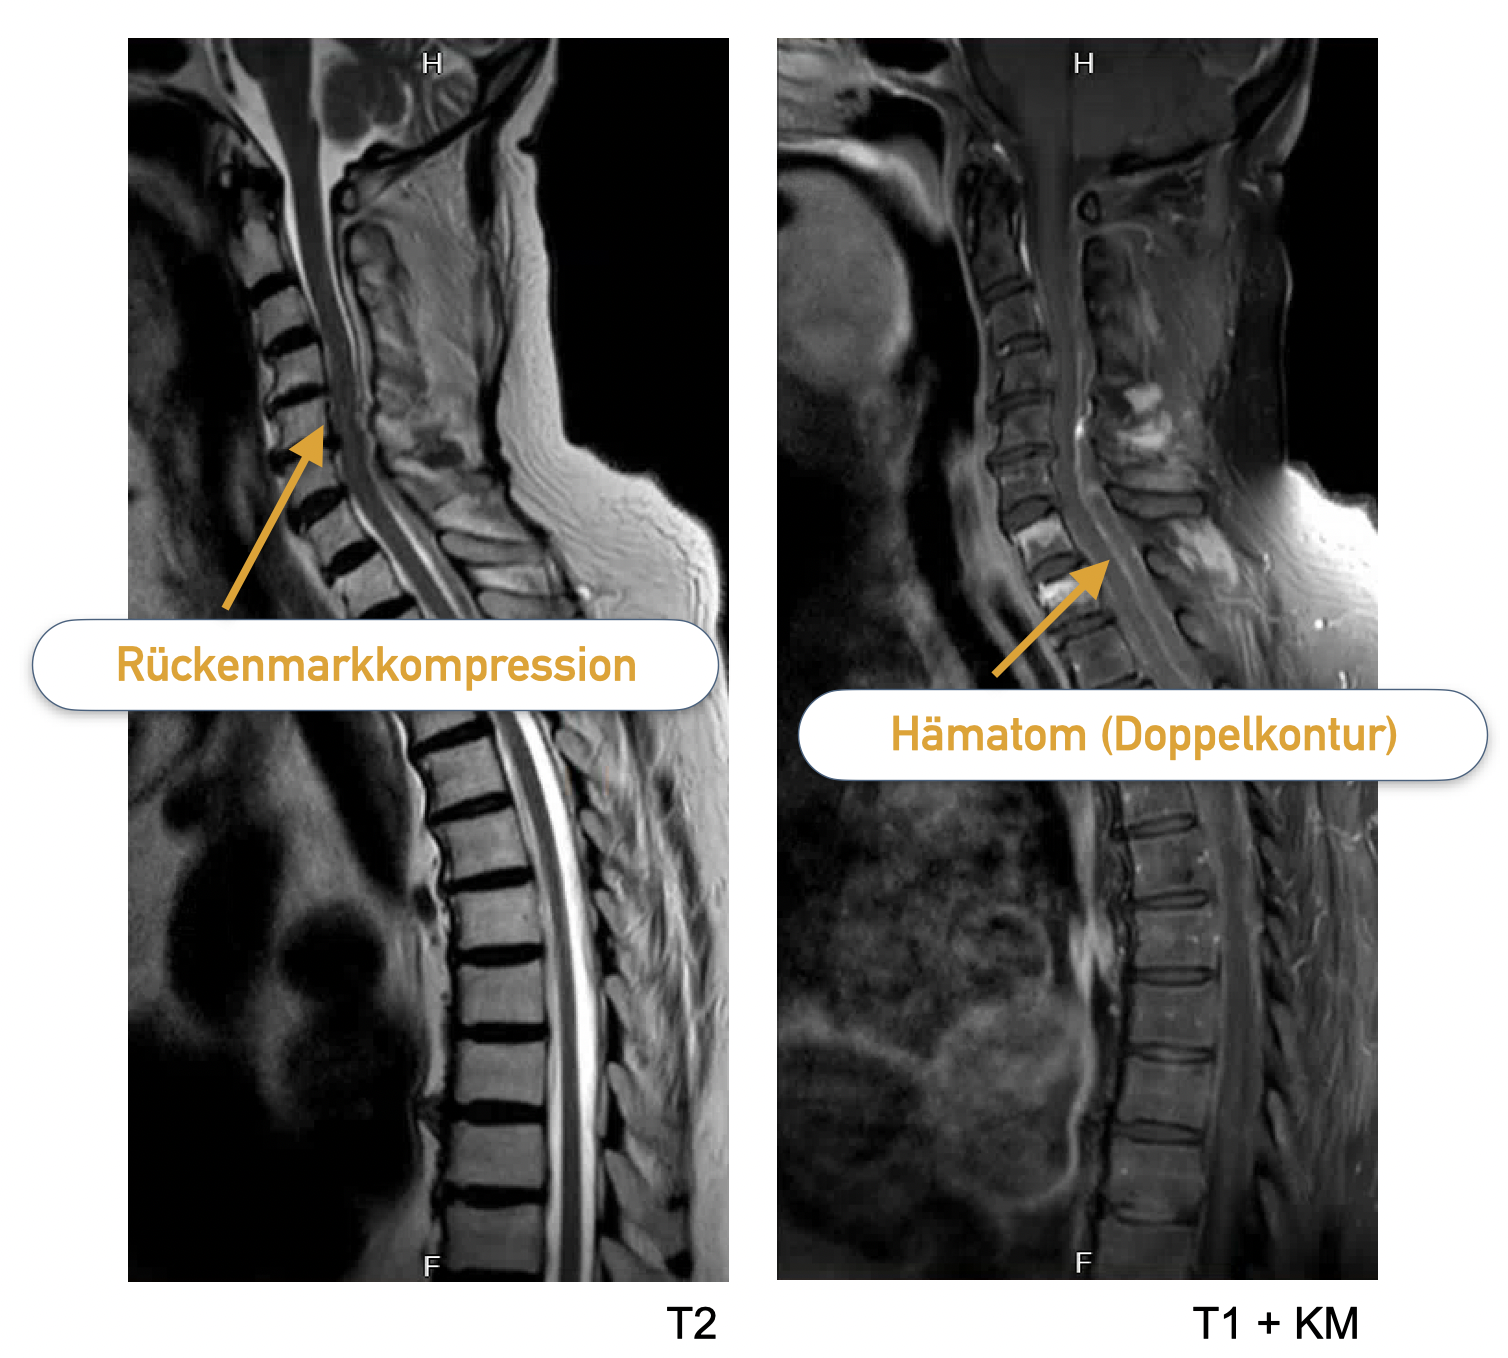

Patientin 2 (noch ein spinaler Notfall)

Zwei Tage später kommt eine über 80-jährige Patient nach einem Treppensturz mit einer rasch zunehmenden Querschnittslähmung zur Aufnahme. Auch sie nimmt Rivaroxaban (Xarelto) als OAK bei Vorhofflimmern ein.

In einer Notfall-MRT zeigt sich ein epidurales (im Rückenmarkkanal, außerhalb der harten Hirnhaut) Hämatom mit Kompression des Rückenmarks.